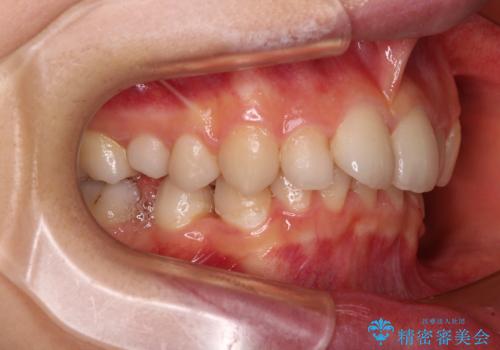

- 後続永久歯の欠損によるスペースと残存乳歯、深い咬み合わせを気にして来院された患者様です。

乳歯を残し、欠損部位のスペースを適正な幅に拡大し、インプラント補綴治療により歯列を整える治療も考えられましたが、ご本人から飛び出している前歯をどうしても引っ込めたいとの要望があったため、残存乳歯ならびに上顎左右第二小臼歯を抜歯して、歯列を整えることとしました。